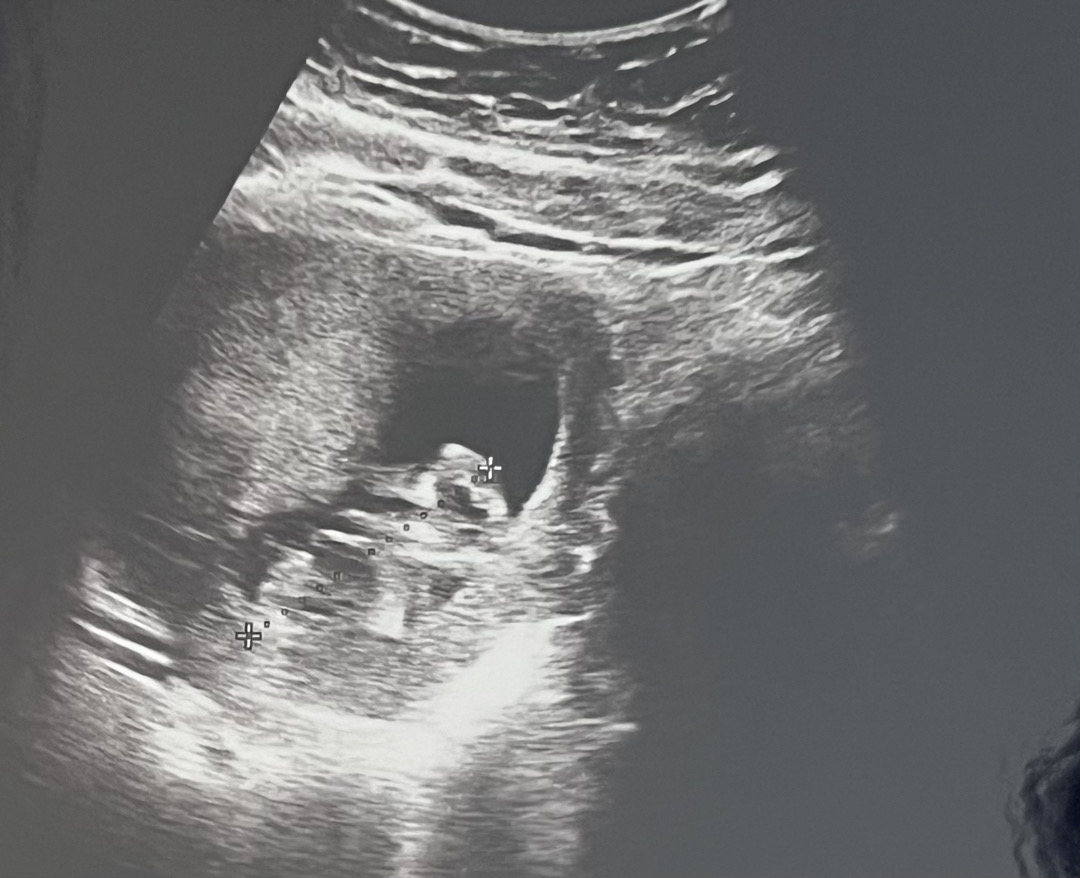

초음파 이상하게 찍어주는 병원 ㅡㅡ

병원비 12주때 바우처 카드 40만원 남았다고 올린 사람입니다 이게 12주 때 촘파보러간건데 ㅋㅋㅋ 어이가없우서… 병원 옮기고싶은데 1차 기형아검사를 여기서 해서 , 2차 기형아검사를 다른데서 하는 방법은 없을까요???? 제발 ㅠㅠ 알려주세요 병원때문에 스트레스받아서 너무 옮기고싶어요